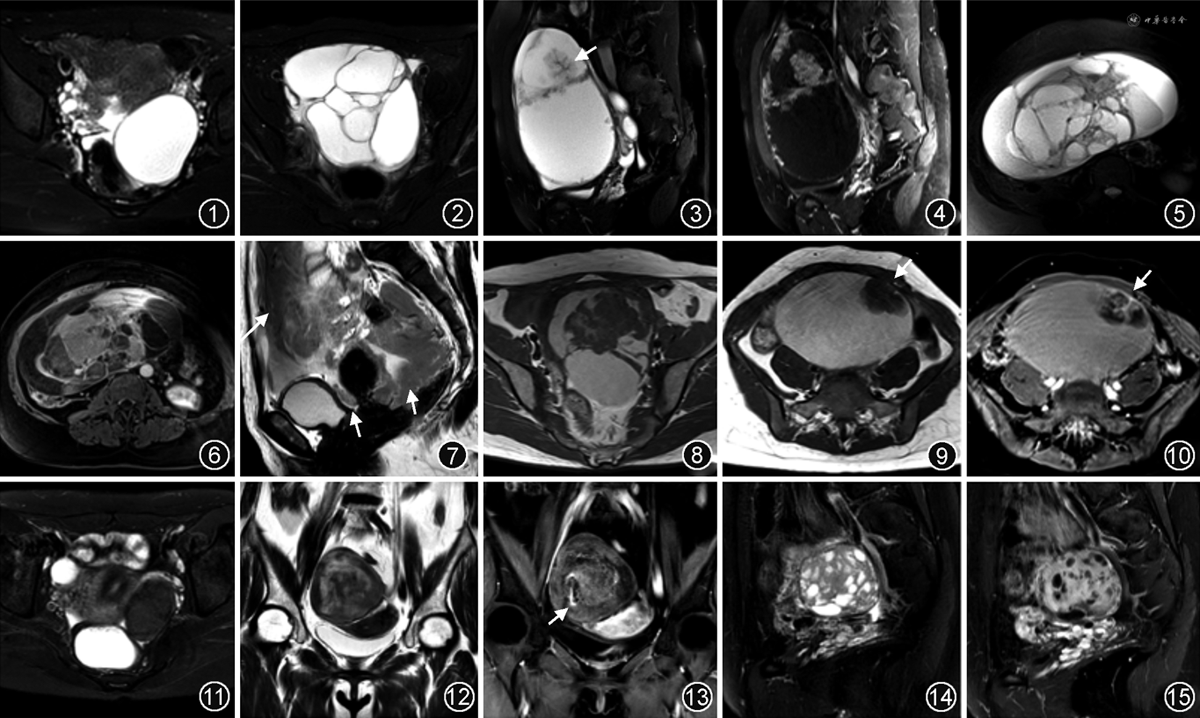

1.浆液性囊腺瘤:最大径多为3~12 cm,平均7.5 cm。绝大多数为单侧、单房或寡多房、类圆形纯囊性肿块,囊液呈均匀水样信号,约10%可呈T1WI和T2WI高信号(图1);囊壁和分隔薄而光滑,T2WI偶见低信号的微小乳头(<5 mm),增强后轻度强化。

2.黏液性囊腺瘤:典型MRI表现为椭圆形巨大多房纯囊性肿块(图2),直径多>10 cm,分房大小及形态不一,可见“囊内囊”。70%以上的肿瘤以水样信号为主,部分分房囊液T1WI呈等或高信号,T2WI呈高、等或低信号。少数肿瘤呈单房囊性肿块,与浆液性囊腺瘤相似。多数肿瘤囊壁及分隔薄而光滑,增强后囊壁和分隔呈轻中度强化[3, 4]。

1.交界性浆液性肿瘤(serous borderline tumor,SBT):最多见,占交界性上皮性肿瘤的50%~70%[4, 5, 6],可单侧或双侧发生,双侧约占37%。MRI表现分3种类型:(1)囊性肿块伴乳头状突起(61%),表现为单房或寡多房,囊内壁及分隔见多发大小不等的乳头状突起(图3,4);(2)实性肿块(11%),卵巢表面外生性实性肿块,内可见形态基本正常的卵巢;(3)囊实性肿块(28%),同时具有囊性和实性SBT的特点[6, 7]。实性成分内含T2WI低信号、弱强化的纤维分支结构是SBT特征性表现[7]。

2.交界性黏液性肿瘤(mucinous borderline tumor,MBT):东亚较欧美发病率高,可达70%[5]。MBT以单侧发生为主,典型MRI表现为:(1)多房囊性为主的肿块;(2)蜂窝状分房,即大量直径为5~10 mm的分房聚集分布;(3)彩色玻璃征(stained-glass sign),因不同分房囊液的黏稠度及蛋白含量不同,T1WI和T2WI显示不同的信号强度,含T1WI高信号或T2WI低信号的分房(图5,6);(4)囊壁及分隔厚(>5 mm)[4,8]。

1.卵巢浆液性癌(serous ovarian carcinomas,SOC):为最常见的EOC,分高级别和低级别SOC,前者占90%。分子水平上,两者为不同的疾病。低级别SOC与SBT的病理及MRI表现相似,常共同存在,术前很难鉴别。多数高级别SOC源自输卵管伞端,MRI表现为囊实性或实性肿块[4,10],直径通常小于10 cm,半数以上累及双侧卵巢。壁结节是上皮性肿瘤的典型影像学特征,高级别SOC的壁结节可为内生性或外生性,大小0.2~4.5 cm,多数以宽基底与囊壁相连。实性成分扩散明显受限,增强后中度或明显强化。25%~30%患者可出现腹腔积液,30%见淋巴结肿大,20%见腹膜、肠系膜和大网膜转移,呈典型的饼状肿块(图7)。

3.卵巢EC和CCC:与浆液性和黏液性肿瘤常见良性和交界性肿瘤不同,卵巢子宫内膜样和透明细胞肿瘤几乎均为恶性侵袭性肿瘤。EC和CCC均与Lynch综合征相关[11],常伴发子宫内膜癌或子宫内膜异位症。(1)卵巢EC最常见于围绝经期女性,多数肿瘤发现于早期。17%为双侧,常为椭圆形、囊性为主肿块,囊壁伴多发大小不等的壁结节或乳头状突起,环囊壁分布[12],单房囊性比多房囊性更常见。约半数EC源自内膜样囊肿,囊液常呈T1WI高信号,实性成分T1WI呈相对稍低信号(图8),DWI扩散受限,完全实性肿块少见。(2)CCC在东亚人群中更常见,发病率较EC高,其典型表现为单房囊性肿块伴单个或多个大小不等的实性乳头状突起(图9,10)。因内膜异位灶周期性出血,囊液常呈T1WI等或高信号,T2WI高信号。实性成分较多时呈囊实性肿块,约1/3的CCC呈完全实性肿块,DWI明显扩散受限,增强后明显强化,与高级别SOC或EC常为中度强化有所不同[4]。

1.纯间质肿瘤:纤维瘤、卵泡膜细胞瘤和纤维卵泡膜细胞瘤为常见的卵巢良性实性肿块[2]。(1)纤维瘤最常见,由成纤维细胞及梭形细胞组成,无雌激素活性;单侧多见,呈类圆形或分叶状实性肿块,T2WI呈特征性低信号(图11),与子宫肌瘤相仿,DWI扩散不受限呈低信号,即“双低实性”,增强后多数呈轻度延迟强化;较大肿瘤可发生水肿变性,表现为片状T2WI高信号及弱强化;也可发生囊变,可呈囊实性肿块。部分富细胞性纤维瘤T2WI可呈中高信号,DWI扩散受限,增强后显著强化。(2)卵泡膜细胞瘤源自卵泡膜细胞,多见于绝经期女性,10%见于年轻女性,约90%为单侧。MRI表现与纤维瘤相仿,总体呈“双低实性”,但T2WI可见云絮状稍高信号的卵泡膜细胞团,后者呈中度强化(图12,13),少数可呈明显强化。(3)纤维卵泡膜细胞瘤为纤维瘤和卵泡膜细胞瘤的混合类型,表现可兼具两者特性[3]。

2.纯性索肿瘤:颗粒细胞瘤是最常见的卵巢恶性性索-间质肿瘤,分为成年型(95%)和幼年型(5%)。成年型多见于围绝经期女性,常有雌激素升高表现;幼年型多见于儿童及青春期,可伴有假性性早熟、月经不规则或闭经。多数肿瘤体积较大,呈圆形、卵圆形或轻度分叶状,边缘清晰。MRI表现多样[4,13],典型者为囊实性或海绵状实性肿块(图14,15),前者表现为实性肿块内多个囊性区,囊液常伴出血,T1WI脂肪抑制和T2WI均呈高信号,可见液-液平面;后者表现为实性肿瘤内多发小囊性区、出血和坏死区。肿块实性成分DWI扩散受限,增强呈中度或明显强化。部分肿瘤呈完全实性,或呈多房囊性,与黏液性囊腺瘤相仿。由于肿瘤有雌激素活性,常见子宫增大,内膜增厚。